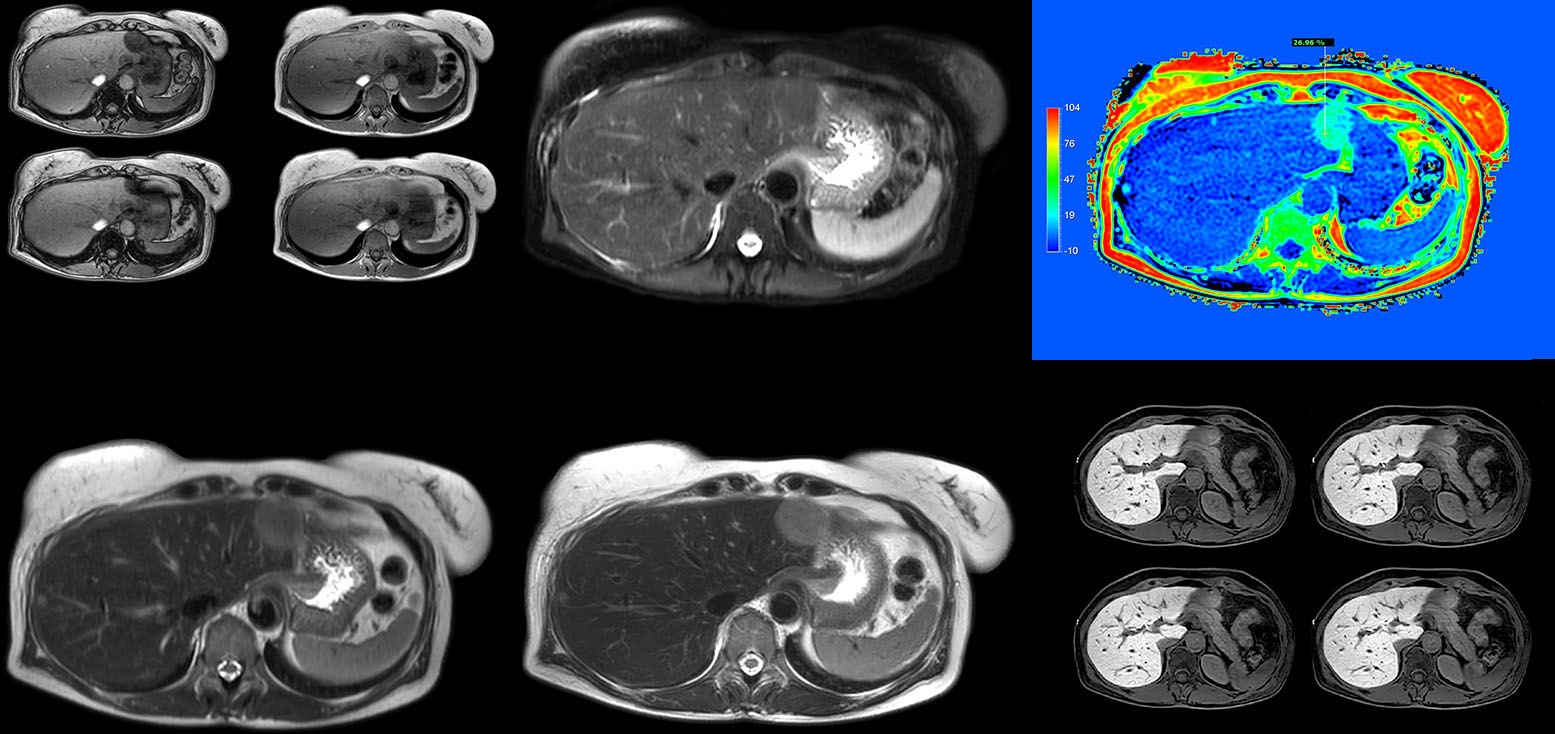

Robust motion correction and high spatial resolution with MultiVane XD

“Using MultiVane XD motion correction, we are now able to acquire high spatial resolution T2-weighted images without seeing relevant motion,” says Dr. Kukuk. “It’s a great technique to obtain high spatial resolution images of the pancreas or the liver, as well as the surrounding organs and tissues. MultiVane XD can be combined with dS SENSE parallel imaging, allowing us to reduce specific absorption rates (SAR), acquire high spatial resolution in short acquisition times, and at the same time reduce artifacts caused by motion in adjacent tissues and organs.”

“In comparison to single shot T2-weighted TSE, this approach with MultiVane XD motion suppression provides higher spatial resolution. In addition, it is especially valuable in patients who cannot hold their breath or have some disabilities. My impression is that this sequence has the potential to substitute for, or even replace, the T2-weighted single shot sequence in our liver exams, because of good and consistent delineation of small lesions.”

Non-invasive liver fat quantification in a breathhold with mDIXON Quant

“Fatty liver disease is a common condition. Studies found a prevalence of non-alcoholic fatty liver disease in up to 44% in the general European population [1]. Liver fat cannot be quantified by ultrasound or CT, so biopsy has been the way to quantify fatty liver disease so far,” says Dr. Kukuk. “mDIXON Quant now allows non-invasive quantification of liver fat, which is valuable for both diagnosis and follow-up during dietary changes or therapy, for instance in hepatitis C.”

“The mDIXON Quant fat fraction maps provide quantitative information and also anatomical detail. The sequence is fast, usually taking about 16 seconds, which is just a breath hold for most patients. It definitely improves our efficiency.”